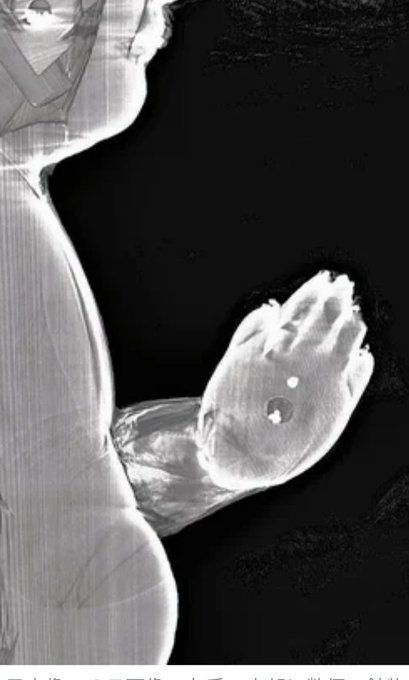

聖徳太子が建立したとされる法起寺に伝わる聖徳太子像を

CTスキャンで調べたところ

合掌する手の内部に鉱物が

納められていることが

奈良国立博物館の調査で判明。

合掌した太子の手のひらから

仏舎利(仏陀の遺骨)が

こぼれ落ちたとする説話に、忠実になぞらえて制作。